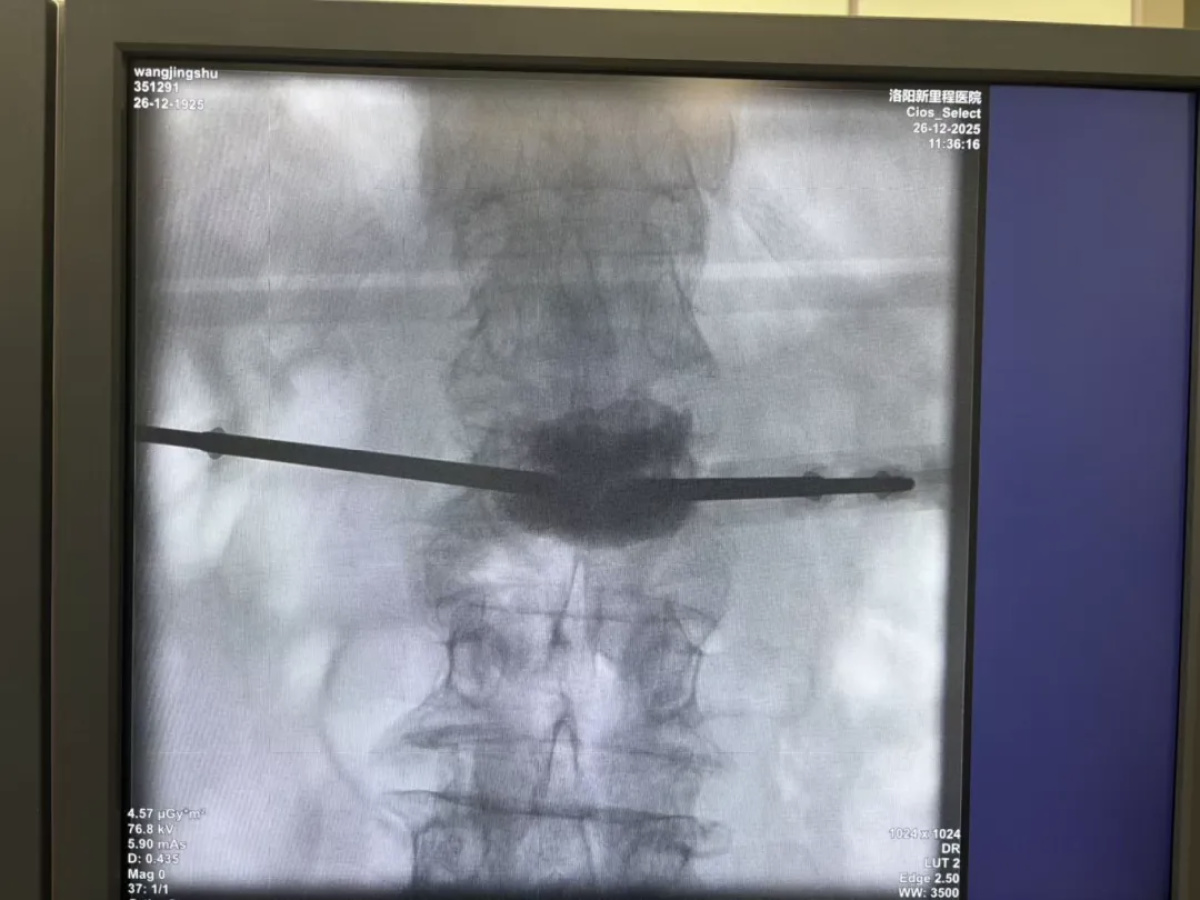

经过周密讨论,团队最终决定实施“L2椎体经皮穿刺球囊扩张+骨水泥成形术”。该术式属于微创手术,仅有穿刺针眼大小伤口,出血极少,对身体干扰小,手术时间短,非常适合高龄、体质弱的患者。

手术由康辉主任主刀。团队通过C形臂X光机精准定位,经皮肤穿刺将特制球囊送入骨折椎体,扩张球囊恢复椎体高度,再注入“骨水泥”稳定骨折。整个过程仅耗时约40分钟,患者生命体征平稳。